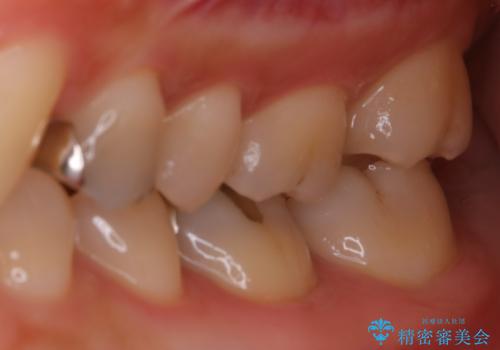

適合のよいセラミックで自分の歯となじむ自然な仕上がりに

- 大きく口を開けると目立つ銀歯のやり替えをご希望された患者様です。適合のよいセラミックインレーで補綴することで、将来的な虫歯発生のリスクを最小限に抑え、機能面でも安心して使っていただけるようにしました